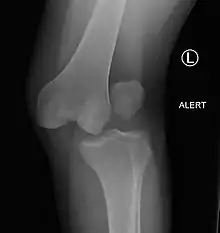

Plain lateral X-ray of the left knee showing a posterior knee dislocation[1]